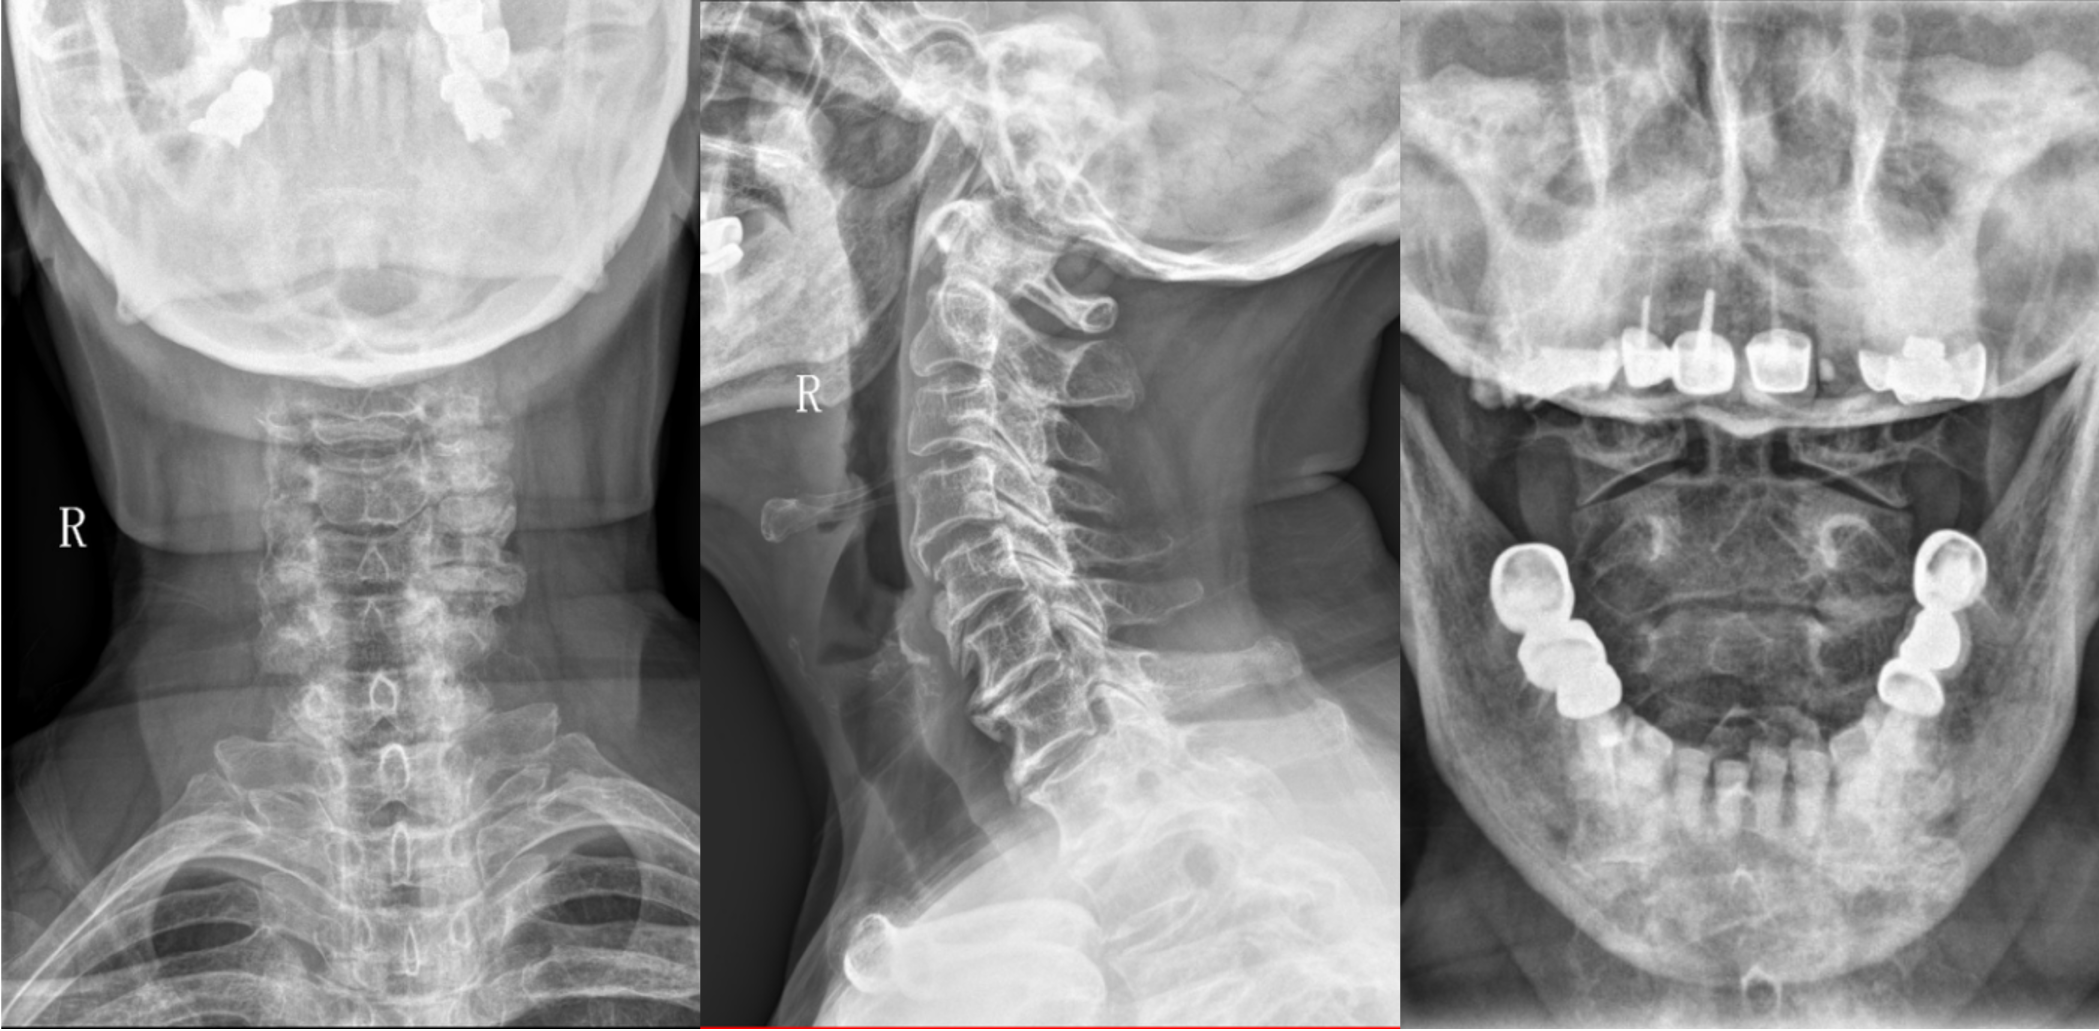

【影像】颈椎X线片见颈椎骨质疏松,广泛性骨质增生,多节段失稳,C4-5、C6-7明显,C6-7椎间隙变窄,寰枢外侧关节对合不全,枢椎棘突偏左。

患者X线片见两侧寰齿间隙差不明显,寰齿前间隙无明显增宽,而其临床表现却是寰枢关节半脱位的常见症状,且手法正骨后可缓解,让我们不得不重新思考现在寰枢关节半脱位X线诊断标准的可靠性。北京罗氏正骨手法治疗后症状消失,说明理筋正骨手法治疗本病有效,而本次治疗只理筋而未正骨,同样取得疗效,证实理筋治疗本病有效,而正骨治疗本病的有效性及“正骨”的起效机理则有待进一步探讨。